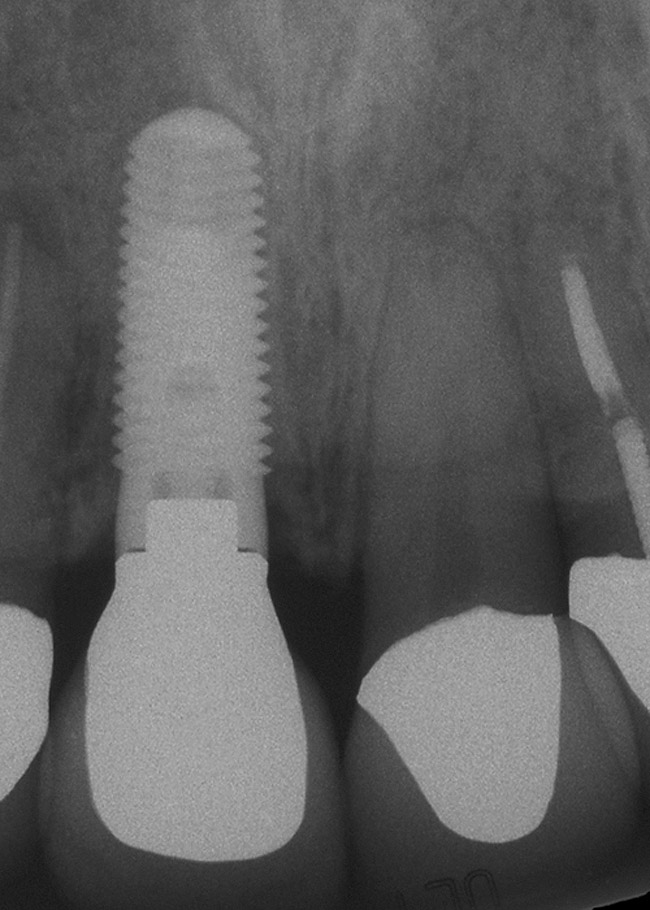

Figure 5h  Postoperative radiographs.

Figure 5h

Figure 5g  Postoperative radiographs.

Figure 5i